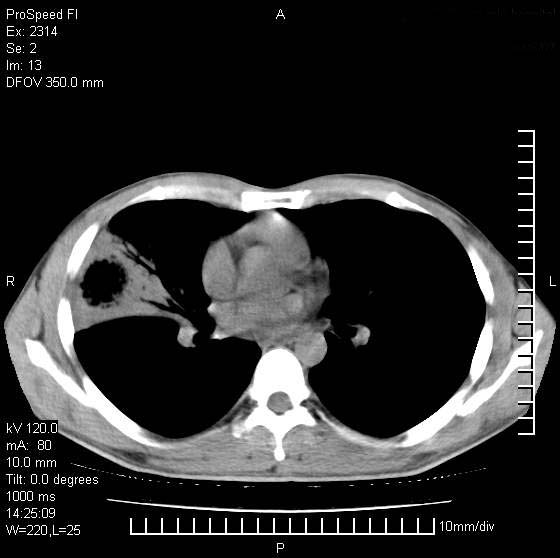

男性,再生障碍性贫血,入院前发热10天,最高40c,右侧胸痛,外院ct示右上,中肺边缘模糊的球性影(就是我现在图中标示的范围),考虑炎症,在我院使用头孢呋辛,洛美沙星10天,高烧消退,自感下午稍有发热,但今天ct示右上,中肺病灶明显扩大,还是考虑炎症,看其中的球型影是否霉菌感染??,是否能排除结核?

右肺中叶外侧段病变,上缘界限不清,下缘锐利,以段性发病为主,内见巨大空洞及空洞内容物,结合病史首先考虑:化脓性肺炎。不除外霉菌感染!

考虑霉菌感染.理由1\\有临床基础疾病,2\\有坏死的空腔,其内可见软组织影.

片状高密度影内见空洞影,内可见球形软组织密度影,并有新月征,考虑霉菌感染.